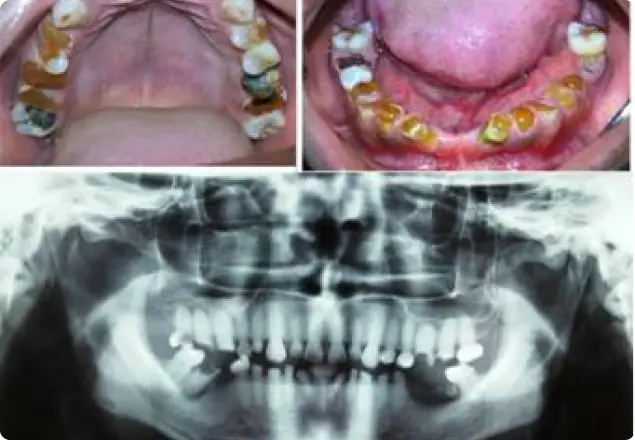

Dentinogenesis Imperfecta